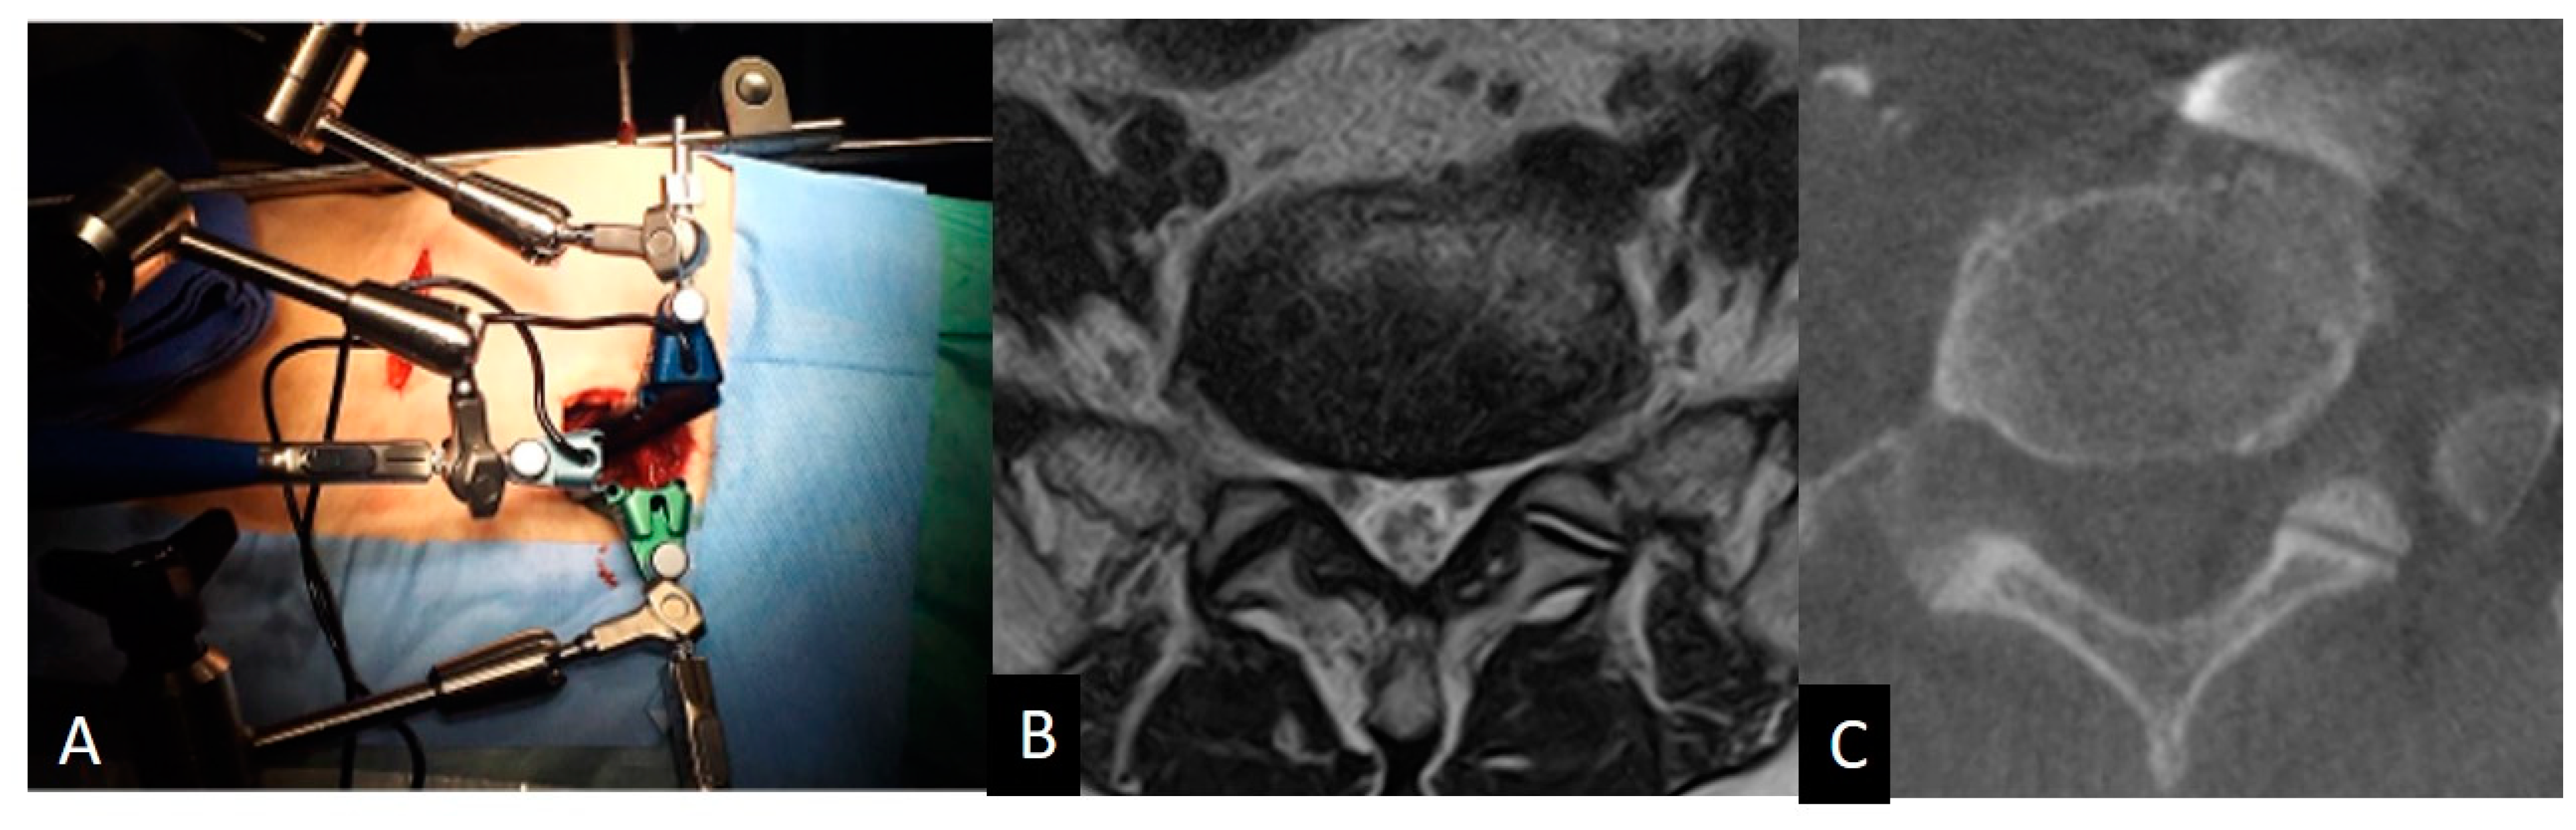

• Case presentation

• Case 1: A 75-year-old woman with L4 degenerative spondylolisthesis and L5/S1 degenerative disc disease received L4-S1 OLIF followed by lateral position percutaneous screwing and fixation. The comparison between preoperative supine MRI images and intraoperative vein-enhanced CT demonstrated left CIV movement of 6.7 mm to the right in the right decubitus position at the L5 lower endplate level, and 3.4 mm to the right at the S1 upper endplate level. The vein bifurcation moved 8.5 mm to the caudal direction under the right decubitus position (Figure 6).

Figure 6. A 75-year-old woman with L4 degenerative spondylolisthesis and L5/S1 degenerative disc disease received L4-S1 OLIF followed by lateral position percutaneous screwing and fixation. The comparison between preoperative supine MRI images and intraoperative vein-enhanced CT demonstrated left CIV movement of 6.7 mm to the right in the right decubitus position at the L5 lower endplate level, and 3.4 mm to the right at the S1 upper endplate level (arrows). The vein bifurcation moved 8.5 mm to the caudal direction under the right decubitus position.